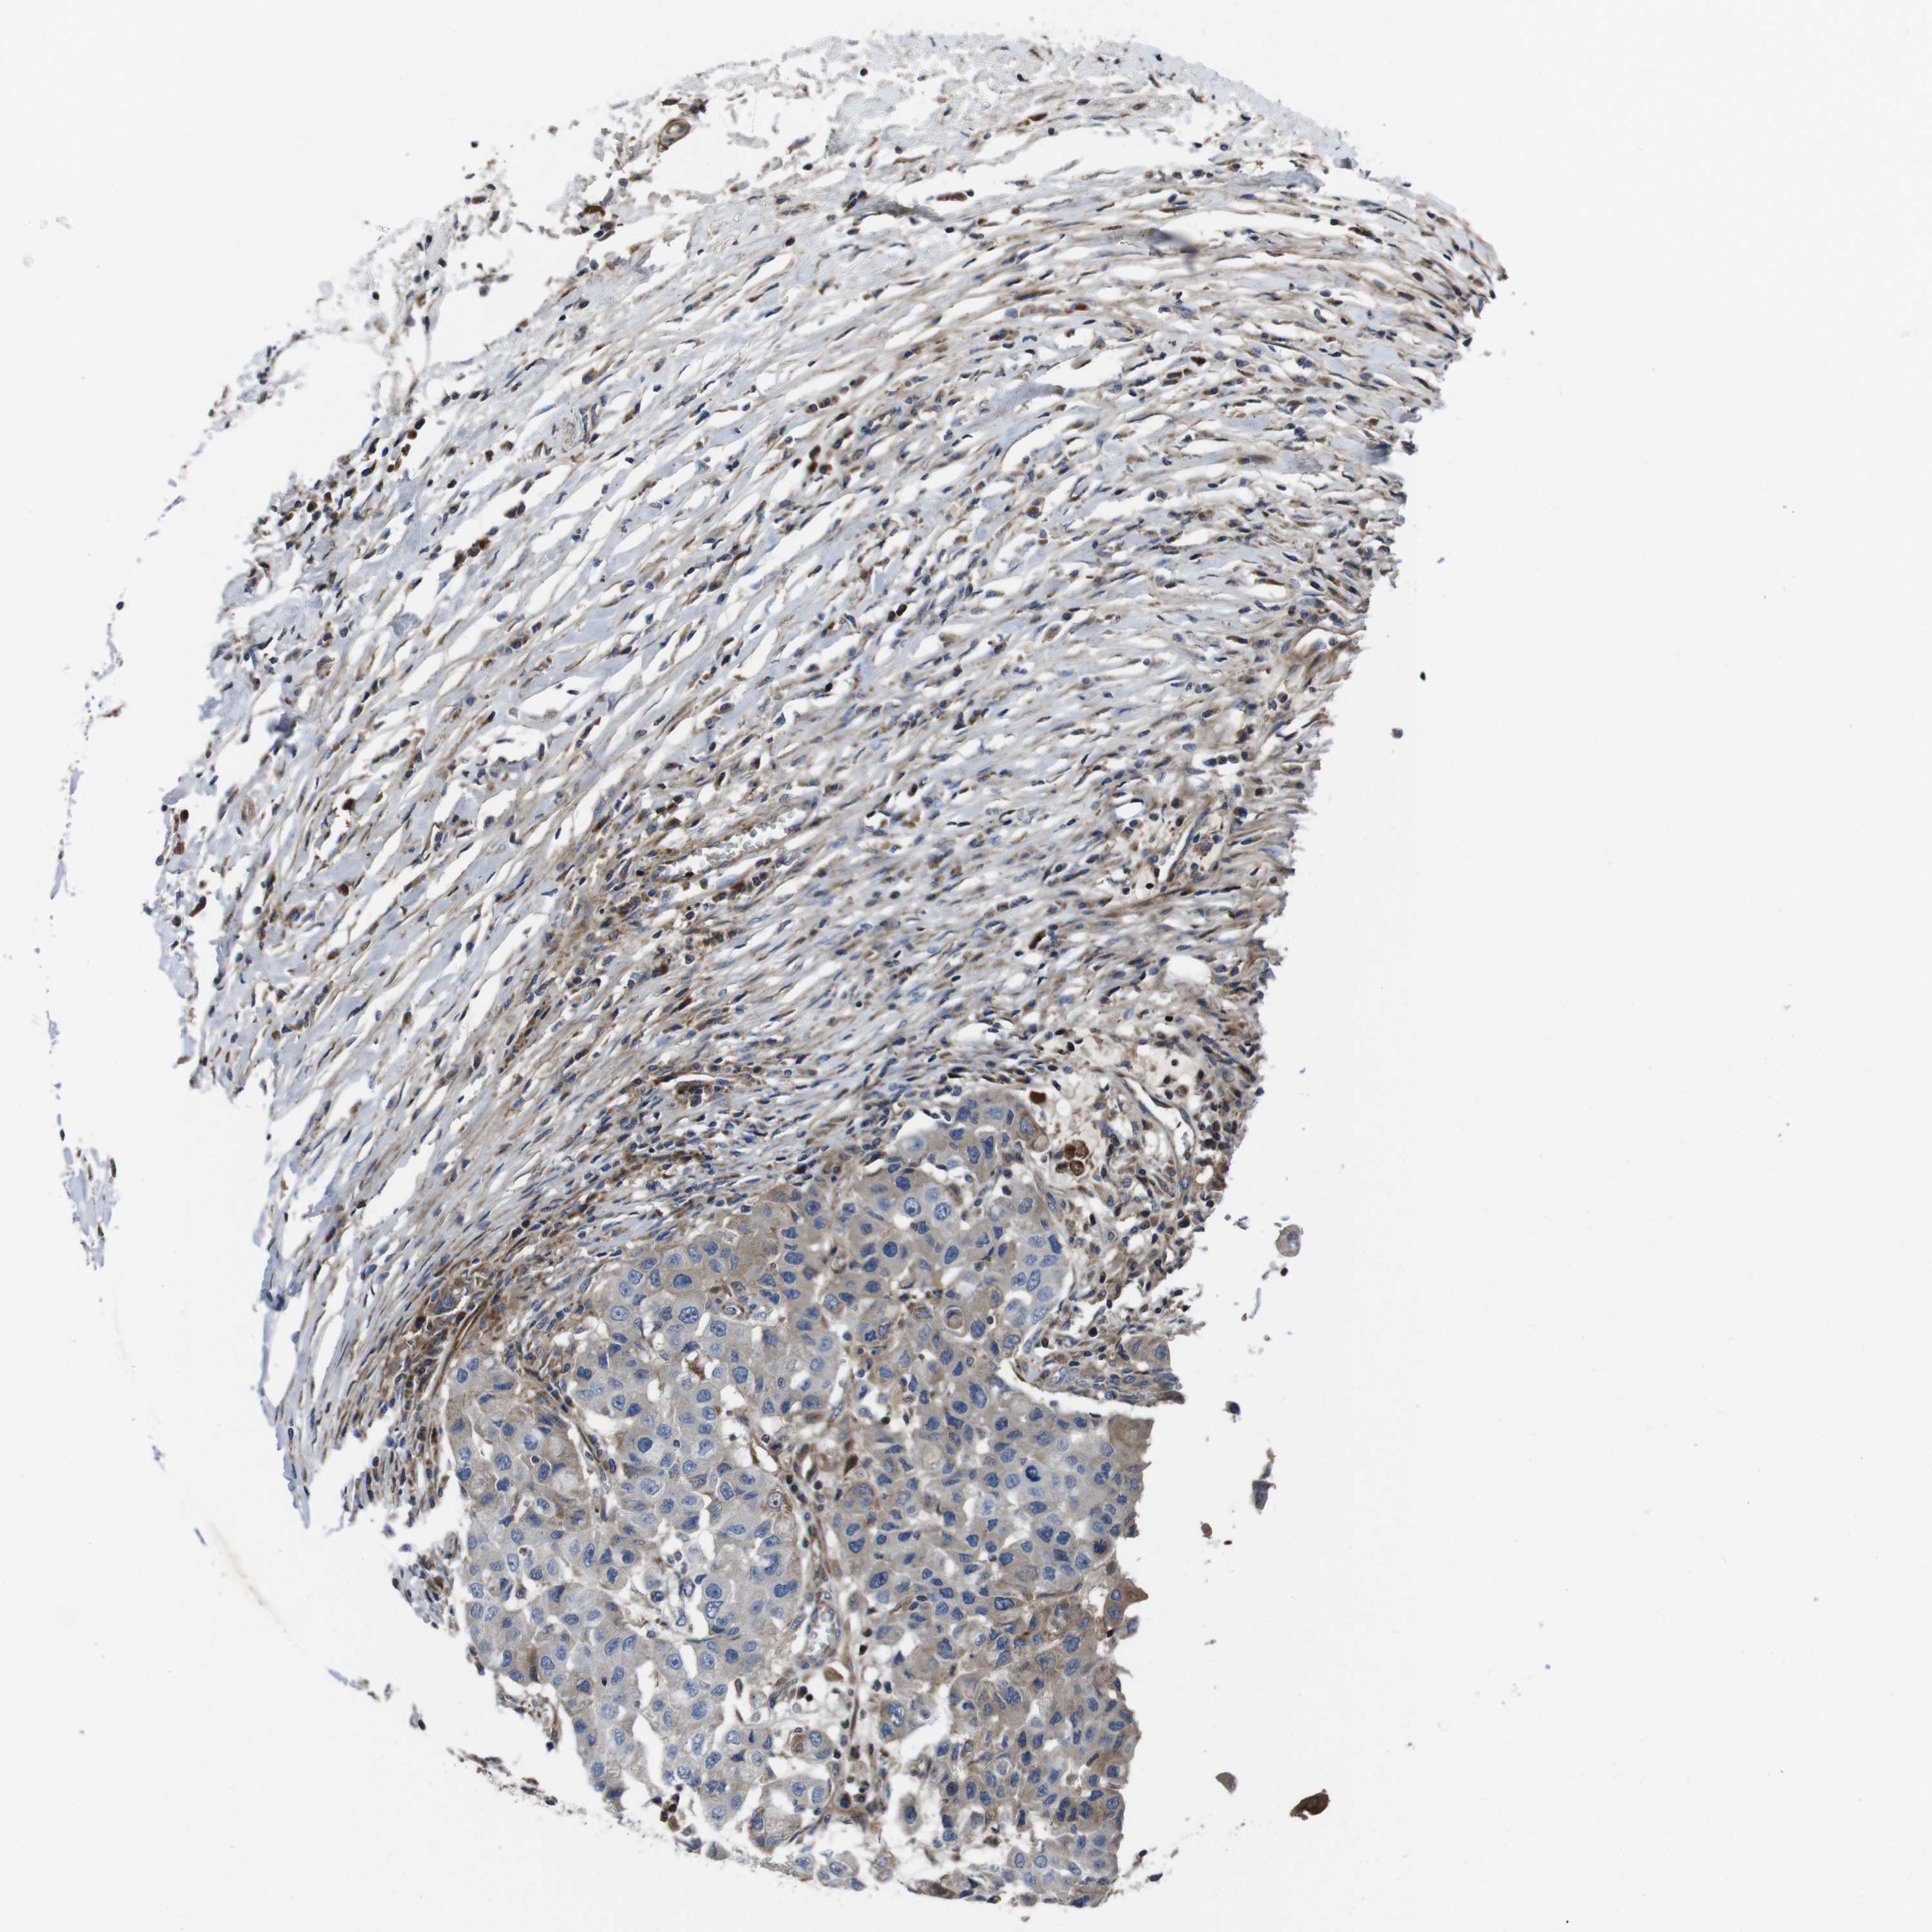

BRCA TCGA BRCA VALIDATION PROTEIN EXPRESSION

ANTIBODIES

AND

VALIDATION